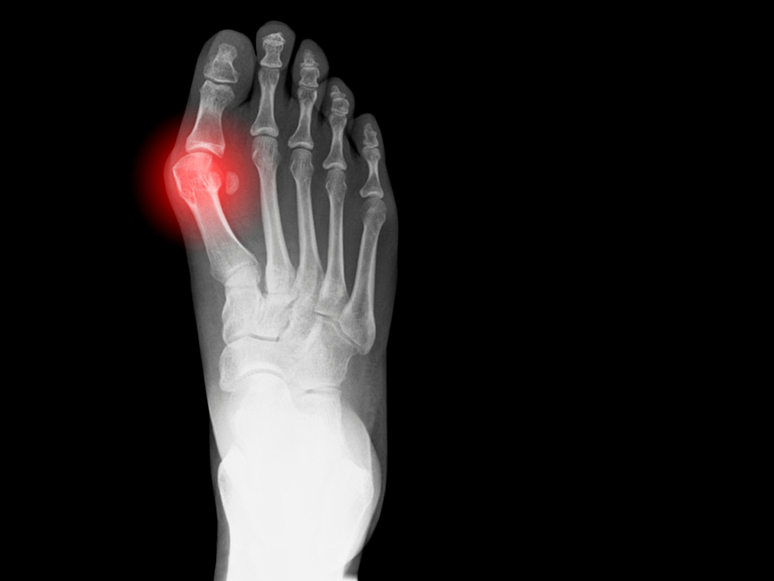

Não é incomum a presença de joanetes em pessoas entre 18-65 anos e é uma condição humana, já que essa protuberância foi encontrada em ossos de mais de mil anos de idade. Mas o que intriga até hoje os cientistas é o motivo dela existir, já que, teoricamente, não faz sentido evolutivo.

Também conhecido como hallux valgus, joanete é um problema que afeta o hallux, ou o dedão, e "empurra" ele em direção aos outros dedos do pé, consequentemente aumentando a largura do pé.

Esse problema pode causar sintomas que interferem na vida de quem o tem, como dores, inchaço, pode causar problemas nos outros dedos, inflamação e até limitar o movimento. Há diversos tratamentos para diminuir o crescimento da joanete, mas quando ele chega ao estado final o único jeito de lidar com ela é com uma cirurgia que retira uma parte do osso e rearranja o dedo.